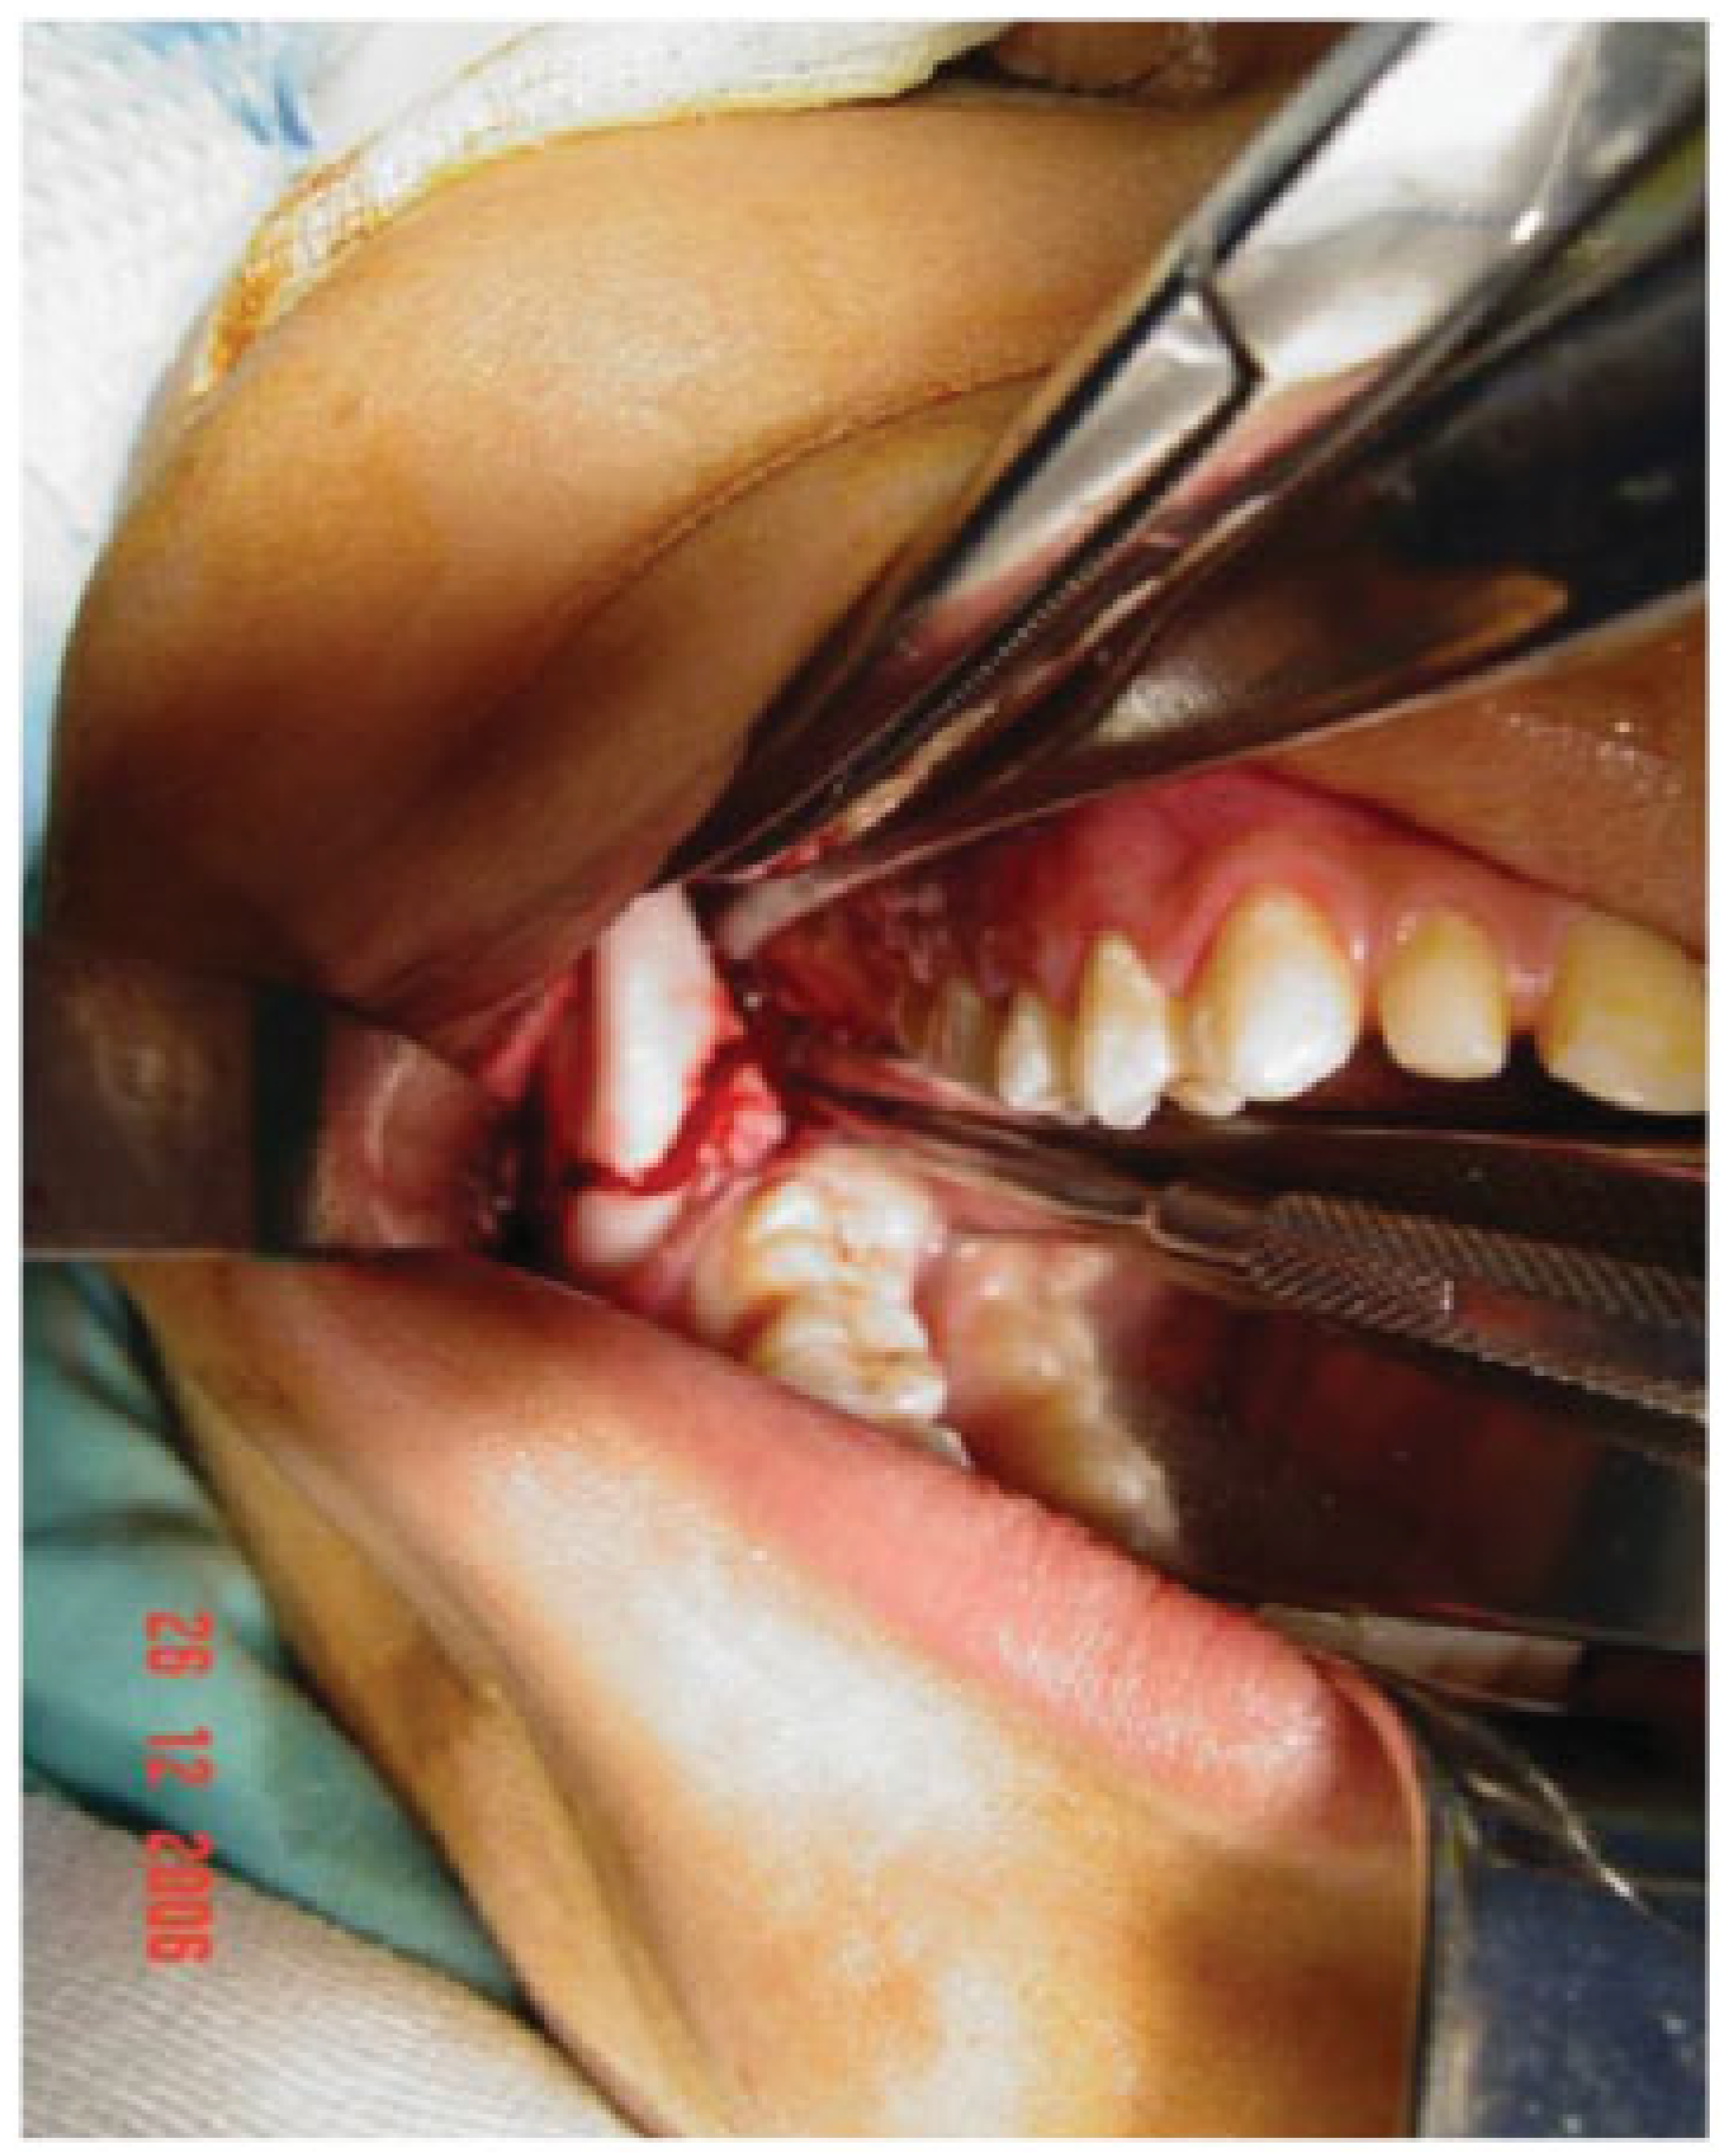

Preoperative assessment of the mandible prior to making the osteotomy cuts and placement of the distractor was assisted by the use of an OPG. The osteotomy cuts (Figure 11) have been previously described [3,4].

As the patient was young, it was deemed important to ensure that both the boney cuts and placement of the screws to secure the distractor plate were positioned to avoid damage to the roots of the teeth and developing tooth germs (Figure 12). A possible advantage of employing staggered buccal and lingual osteotomy cuts is that the width of the mandible is preserved as the callous is elongated as opposed to the formation of a narrow callous that might arise from a single vertical buccal-lingual osteotomy cut. However, the use of sagittal split osteotomy cuts results in a large surface area between the buccal and lingual plates for rapid healing to take place; consequently, distraction was started on the first postoperative day rather than on the fifth postoperative day with the standard vertical cut [5].

Figure 11. Modified mandibular sagittal split osteotomy cuts made prior to placement of the mandibular ramus distractor.